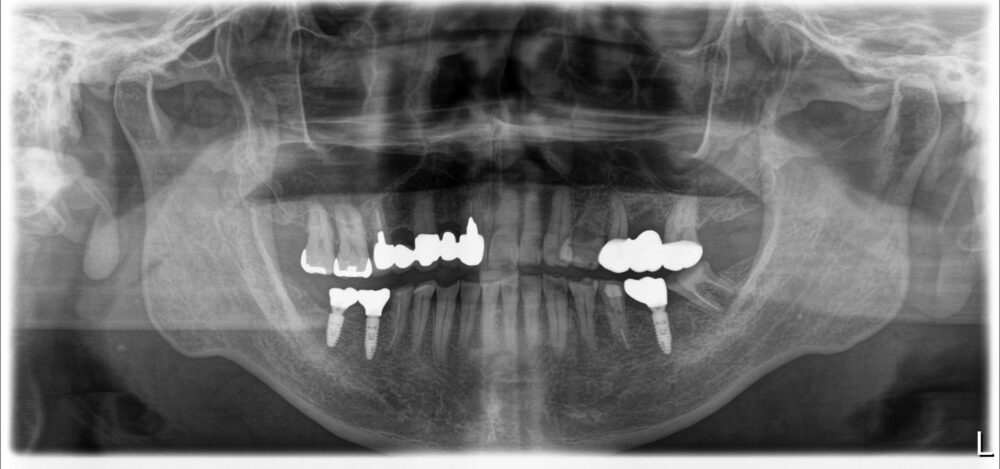

症例2

治療後

| 主訴 | 左上奥歯痛い |

|---|---|

| 診断 |

左上6歯根破折 |

| 治療内容 | 左上6インプラント抜歯即時埋入 |

| 年齢・性別 |

66歳、女性 |

| 治療期間 |

6ヶ月 |

| 治療費用 | 診査診断¥22000+一次オペ(アストラ)¥330000+GBR¥110000+¥上部構造¥143000 合計¥605000 |

| リスク・副作用 | インプラント周囲炎、上部構造の緩み |